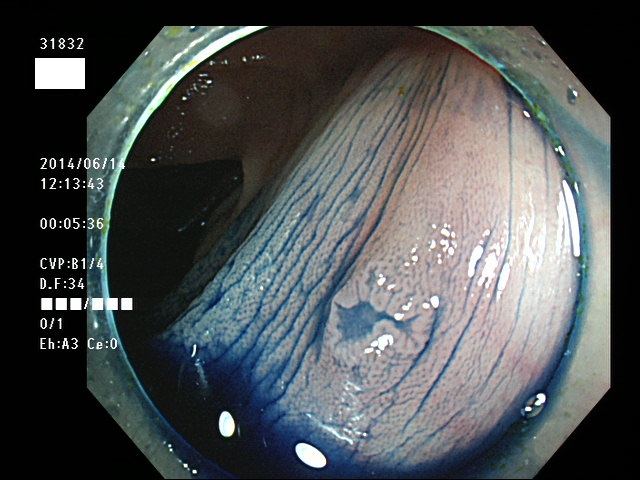

上記100名より抽出した平坦・陥凹型腺腫(=癌化の危険が高いが見落としやすい病変)の内視鏡写真